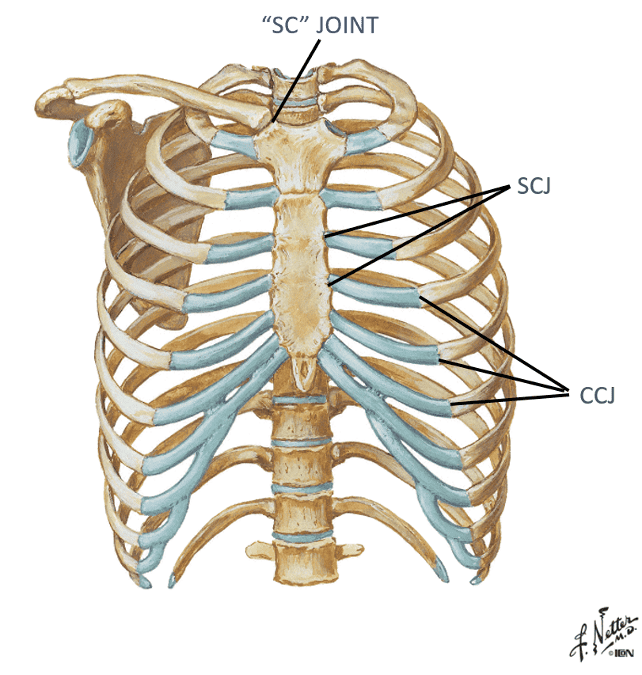

Identify/describe the joints of the anterior thorax...what are they articulations with?

- Costochondral joints?

- Sternocostal joints?

- Sternoclavicular joint (“SC” joint)?

Costochondral joints...Rib articulation with costal cartilage

Sternocostal joints ...articulation between costal cartilage and

sternum

Sternoclavicular joint (“SC” joint) ...Articulation

between sternum and clavicle